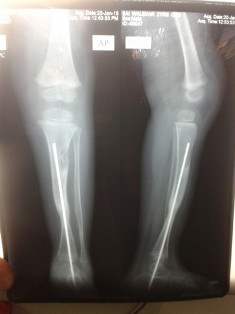

This is a relatively rare condition in which the parents will complain of anterior or anterolateral bending of tibia (shin bone). The bowing can become apparent around 6 months of age. It goes on progressing and then the child will present with a fracture. There are mainly two types. Dysplastic type in which there is narrowing and sclerosis and cystic type in which there are cyst like areas. It may be associated with neurofibromatosis.

The non union site needs to be excised and an intramedullary rod is inserted to prevent refracture. Bone grafting is also required. The management of this condition is difficult and repeated surgery may be required. In older children Ilizarov method for compression and lengthening can be used to attain union. Newer elongating rods have also been used with good results.